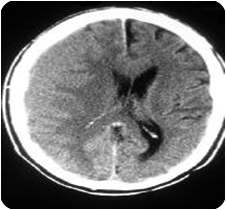

Fraktur os temporal kanan, kedudukan baik. Extracranial tampak soft tissue swelling di puncak parietal kiri. Tampak perdarahan contusio di temporal kanan dan perdarahan subarachnoid di sulcus sylvii kanan, tidak menyebabkan midline shift. Tampak perdarahan epidural kecil ( 4 x 19 mm x 1 slice ) di temporal kiri. Tidak tampak lesi hipo/hiperdens yang mencurigakan infark / s.o.l. Differensiasi white dan gray matter baik, tidak tampak shift dari midline strukutur. Susunanventrikel di tengah, simetris dan sedikit menyempit. Perifer sulci, sulcus syvii dan basal cisterna menyempit. Cerebellum dan batang otak baik.

Kesan :

2.Senin, 8 oktober 2007 Dilakukan CT SCAN Kepala setelah dikonsulkan dengan dr. Spesialis Bedah Saraf dengan klinis contusio cerebri, sehingga diperoleh gambaran CT Scan-nya :

Masih tampak perdarahan di mastoid kiri dan sinus sphenoid kanan. Perdarahan contusio di temporal lobe kanan sedikit bertambah ke parietal bawah, sudah tampak perifocal oedema menyebabkan midline shift 3 mm ke kiri. Perdarahan subarchnoid di sulcus sylvii kanan sulit dinilai karena perdarahan contusio dan udem. Perdarahan epidural kecil di temporal kiri tidak bertambah. Tidak tampak lesi hipodens/hiperdens yang mencurigakan infark/ s.o.l. Differensi white di tengah, simetris dan sedikit menyempit. Perifer sulci, sulcus sylvii dan basal cisterna menyempit. Cerebellum dan batang otak baik.

Dilakukan CT Scan kepala setelah selesai operasi, sehingga diperoleh gambaran CT Scan-nya sbb :

Defect tulang temporoparietal kanan post craniotomy. Masih tampak sedikit sisa perdarahan di temporal lobe kanan dengan perofocal udem sampai ke lateral basal ganglia kanan, tampak sedikit herniasi melalui defect tulang. Lesi infark kecil-kecil di ukleus lentiformis kanan. Mencurigakan perdarahan epidural kecil di temporal kiri. Differensiasi white dan gray matter baik, tidak tampak shift dari midline struktur. Susunanventrikel di tengah, simetris dan tidak melebar / menyempit. Perifer sulci,sulcus Syvii dan basal cisterna tidak melebar / menyempit. Cerebellum dan batang otak baik.